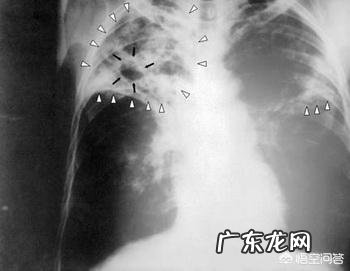

肺结核是由结核杆菌感染的呼吸道传染病 。其传染途径主要是通过空气传播 。患者的痰液有大量的结核杆菌,通过咳嗽、吐痰、打喷嚏将结核菌悬浮在空气中,正常人与患者密切接触亦可感染 。少儿、年老体弱及肺部感染者因抵抗力差易被感染 。肺结核病虽然疗期长,传染性强,对人类健康危害很大 。但该病可防可治,按现有的治疗手段,只要坚持正规治疗,绝大多数患者是可以治愈的 。

肺结核的诊断分为几个部分,疑似病例,临床诊断病例,确诊病例 。

疑似病例:流行病学+临床表现+影像学检查

临床诊断病例:临床表现+肺部影像学检查+结核抗体或T-SPOT阳性,痰涂片阴性

确诊病例:临床表现+肺部影像学检查+痰抗酸染色涂片阳性或痰找到抗酸杆菌痰或痰核酸检测阳性,或痰培养阳性 。这是每一口痰都饱含结核分枝杆菌的病人,应该敬而远之 。

疑似病例和临床诊断病例,传染性很低 。